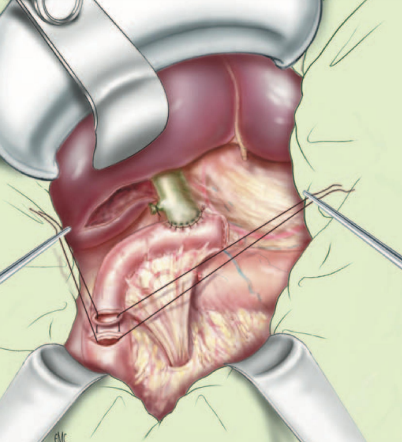

Hình. Mở OMC lấy sỏi qua PT nội soi (A). B. Lấy sỏi bằng pince; C. Bơm nước áp lực cao; D. Dùng rọ Dormia

Khâu chỗ mở OMC: Có 3 phương án:

- Khâu kín thì đầu không dẫn lưu: Là ưu việt nhất, nhưng đòi hỏi kiểm tra không tổn thương phù nề cơ Oddi, đảm bảo sạch sỏi, thành ống mật không viêm mủn nát, không có viêm mủ đường mật;

- Khâu đường mật kèm dẫn lưu Kehr: Kinh điển được dùng cho gần như tất cả BN. Lợi điểm: Chụp đường mật sau mổ kiểm tra, cũng như xử trí tiếp nếu như còn sỏi;

- Khâu đường mật kèm dẫn lưu qua ống túi mật.

Hình. Khâu lại chỗ mở OMC

A – Không dẫn lưu. B – Dẫn lưu Kehr. C – Dẫn lưu qua ống mật